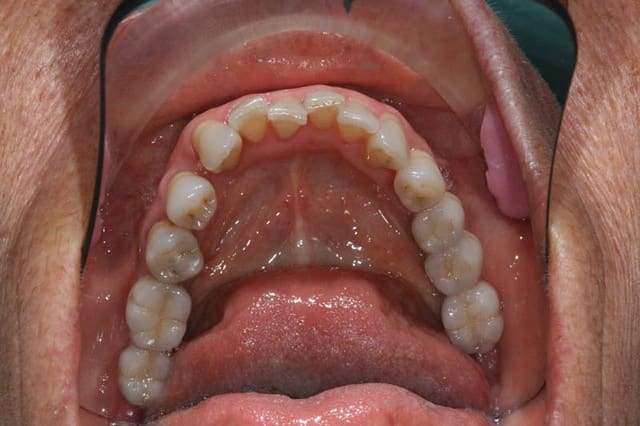

C’est ma préférée

77 ans, un moral d’enfer !

malpositions Inc. Inf. qui déstabilisent son complet du haut

pourquoi, dès qu’on leur fait de la place, 31/41 se mettent à loucher

génotype strabistique

je ne suis pas curieux,

mais je voudrais savoir ...

@+ Bjc.

Une main gauche entiére de décalage annulée par 21,24,25. Regarde bien les pointes des cuspides vestibulaires en 34, 35...